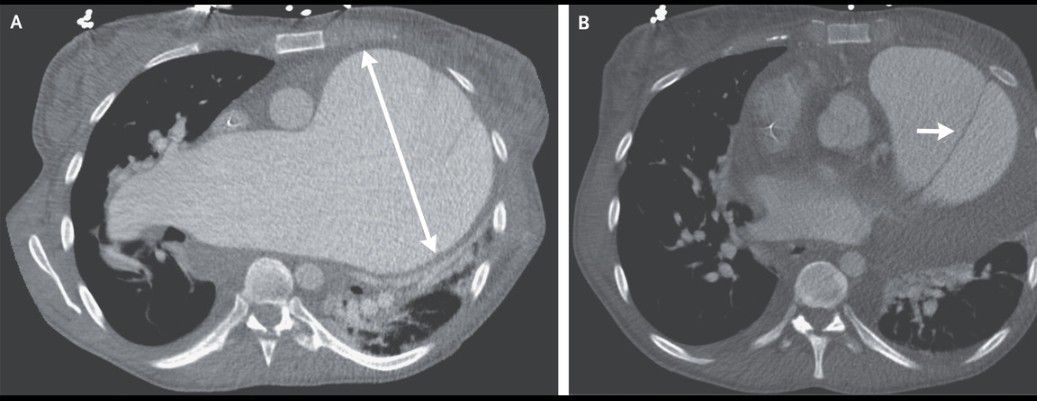

A 35-year-old woman with idiopathic pulmonary arterial hypertension presented to the emergency department with a 1-day history of chest pain. She had been undergoing evaluation for lung transplantation and was known to have a 12-cm pulmonary-artery aneurysm that had been enlarging over the preceding 8 years (Panel A). The heart rate was 101 beats per minute, the blood pressure 109/66 mm Hg, and the oxygen saturation 97% while the patient was receiving 4.5 liters of oxygen per minute. A computed tomographic scan of the chest showed a new dissection flap originating in the main pulmonary artery and extending into the left pulmonary artery (Panel B, arrow). She was admitted to the hospital, where the medications she had been taking — tadalafil, macitentan, and infused treprostinil — were continued, and was listed for urgent lung transplantation. On the day after admission, the hypoxemia worsened and new onset of atrial fibrillation with a rapid ventricular response was observed. Venoarterial extracorporeal membrane oxygenation was initiated and was continued for 2 days, at which time the patient underwent transplantation of both lungs and replacement of the main pulmonary artery and pulmonary valve. Pulmonary-artery dissection is a rare complication of long-standing pulmonary hypertension. Patients may present with worsening chest pain, dyspnea, or shock. The patient was discharged 2 weeks after transplantation and continued to do well 6 months later at follow-up.